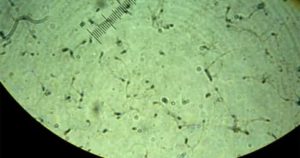

Для оценки подвижности сперматозоидов рекомендуется использовать простую систему классификации по категориям. Для классификации 200 сперматозоидов последовательно просматривают в 5 полях зрения микроскопа (Рис. 1).

Изучение клеточных структур мужского семени при хорошем оптическом увеличении позволяет диагностировать урологическую патологию и узнать многое о сперматогенезе. Достоверность результатов спермограммы во многом зависит от разрешающей возможности оптической техники, а также компетентности специалиста.

При рассмотрении спермы в окуляре микроскопа можно увидеть не только сперматозоиды. Кроме этих жгутиковых элементов, в эякуляте присутствуют клетки округлой формы, не имеющие жгутиков. К ним относятся:

Следует отметить, что не всегда представляется возможным пристально рассмотреть всю «круглую братию». Для этого необходимы приличный микроскоп и хороший специалист, умеющий отличить лейкоцит от незрелого сперматозоида.